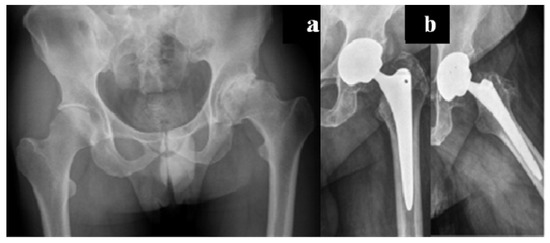

The modern management of haemophilia is usually deemed to be sufficient to prevent any form of hip arthropathy, except in the case of inhibitors. However, patients with recurrent bleeding, with a history of trauma or with associated femoroacetabular impingement are prone to develop haemophilic arthropathy (Figure 1).

Figure 1. Forty-six-year-old haemophilic subject affected by severe haemophilia A, with inhibitors, with symptomatic left hip arthropathy secondary to femoral acetabular impingement.